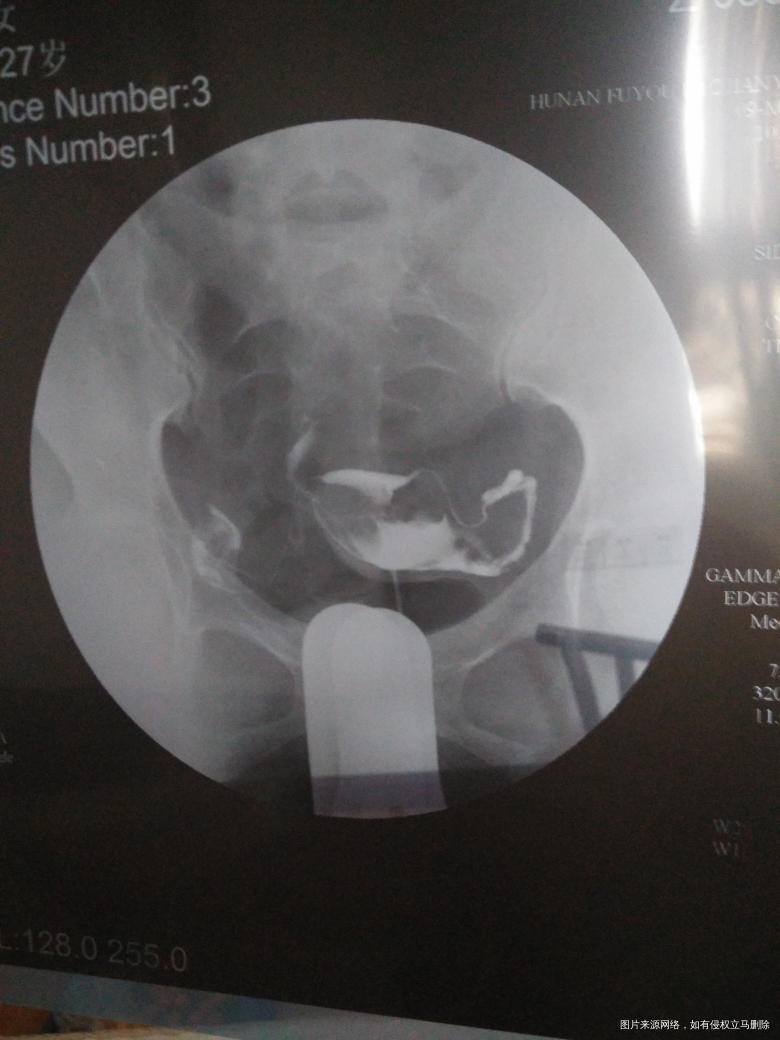

今天做了造影…结果和医生开的药物都在下面…因为拿到结果我的医生下班了…急切请各位医生帮忙看一下…给些建议…并没有流血…是不是可以不吃止血的药!

输卵管造影双侧输卵管通而不畅,有黏连,建议用中药,热敷按摩理疗等治疗后观察复查。

您好,建议服用3-5天预防,另外防止感染,报告看输卵管通而不畅,可以中药灌肠,输卵管通液治疗,祝您备孕成功,记得点击采纳!